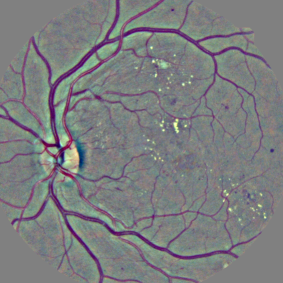

5.4 Visualization Artifacts

Artifacts from various visualization algorithms are illustrated in Fig. 4. First, it can be seen that the original sensitivity criterion is inadequate to finely detect lesions. Sensitivity maps seem to indicate that if lesions grew in size, the diagnosis would be consolidated. The hue constraint prevents the lesion detections from growing. Second, it can be seen that, due to the drafting effect, blood vessels (lesion confounders) in the vicinity of lesions are detected, both in the hue-constrained sensitivity maps and in the layer-wise relevance propagation maps. The resulting false detections are not necessarily connected to the true detection, so they cannot be removed easily through image post-processing techniques: they have to be removed beforehand, hence the proposed approach.

Three ConvNets were trained to detect referable DR in the Kaggle-train dataset, using the proposed heatmap optimization procedure. Then, we evaluated how well those ConvNets could detect lesions in the DiaretDB1 dataset, without retraining them. For lesion detection at the image level, they outperformed previous algorithms, which were explicitly trained to detect the target lesions, with pixel-level supervision (see Fig. 7). This superiority was observed for all lesions or groups of lesions, with the exception of ‘red lesions’. Experiments were also performed at the lesion level: for all lesion types, the proposed algorithm was found to outperform recent heatmap generation algorithms (see Table 3). As illustrated in two examples (see Fig. 9 and 10), the produced heatmaps are of very good quality. In particular, the false alarms detected on the vessels, in the vicinity of true lesions in the unoptimized heatmaps ( maps), are strongly reduced with sparsity maximization (, , ). These experiments validate the relevance of image-level supervision for lesion detectors, but stress the need to optimize the heatmaps, as proposed in this paper. Note that detection performance is not affected much by image quality: very good detections are produced in the blurry image obtained with a low-cost, handheld retinograph (see Fig. 10). This is a very important feature, which opens the way to automated mobile screening. However, it can be observed that the ‘AlexNet’ architecture, which achieves moderate DR detection results, also achieves poor detection results at the lesion level, even after heatmap optimization (see Table 3): to ensure good detection performance at the lesion level, the proposed optimization framework should be applied to ConvNet architectures that achieve good image-level performance.